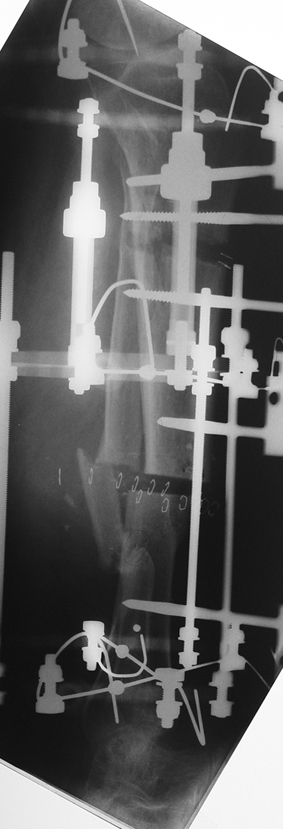

Uygun radikal debridman tüm nekrotik kemik ve yumuşak dokuların çıkartılmasını gerektirir, ve sıklıkla uzuvda instabiliteye neden olur. Kalan kemik ve yumuşak doku defektinin bir şekilde fiksasyonu ve rekonstrüksiyonu gereklidir. İlizarov’un ortaya koyduğu distraksiyon osteogenezi yöntemi, kaynamanın elde edilmesi, deformitenin düzeltilmesi, bacak boy eşitsizliğinin giderilmesi ve segmental defektlerin rekonstrükte edilmesi için başarıyla kullanılmaktadır.

Eksternal fiksatör ile geçen süre (eksternal fiksasyon indeksi), gereken distraksiyon miktarına bağlıdır ve bu süre boyunca bazı komplikasyonlarla karşılaşılabilir. Distraksiyon dönemi sona erdikten sonra, distraksiyon süresinin iki katını aşan konsolidasyon döneminde hastalar eksternal fiksatörü zorlukla tolere edebilirler. Yeterli konsolidasyon sağlanmadan eksternal fiksatör çıkartılırsa ise kırıklar, deformite ve kısalık oluşabilir. Hastanın fiksatör ile birlikte geçirdiği sürenin azaltılması ve böylece hasta konforunun ve aktivite düzeyinin arttırılması için intramedüller çivi üzerinden uzatma yöntemi uygulanmaktadır. Bu yöntemde distraksiyon dönemi sona erdiğinde kemiğin içindeki çivi statik olarak kilitlenmekte ve eksternal fiksatör çıkartılmaktadır. Stabilizasyon intramedüller çivi tarafından sağlandıktan sonra konsolidasyon dönemi gerçekleşmektedir. Bu şekilde hem eksternal fiksatörün uzun süre kalmasından hem de erken çıkartılmasından kaynaklanan komplikasyonların önüne geçilmektedir.